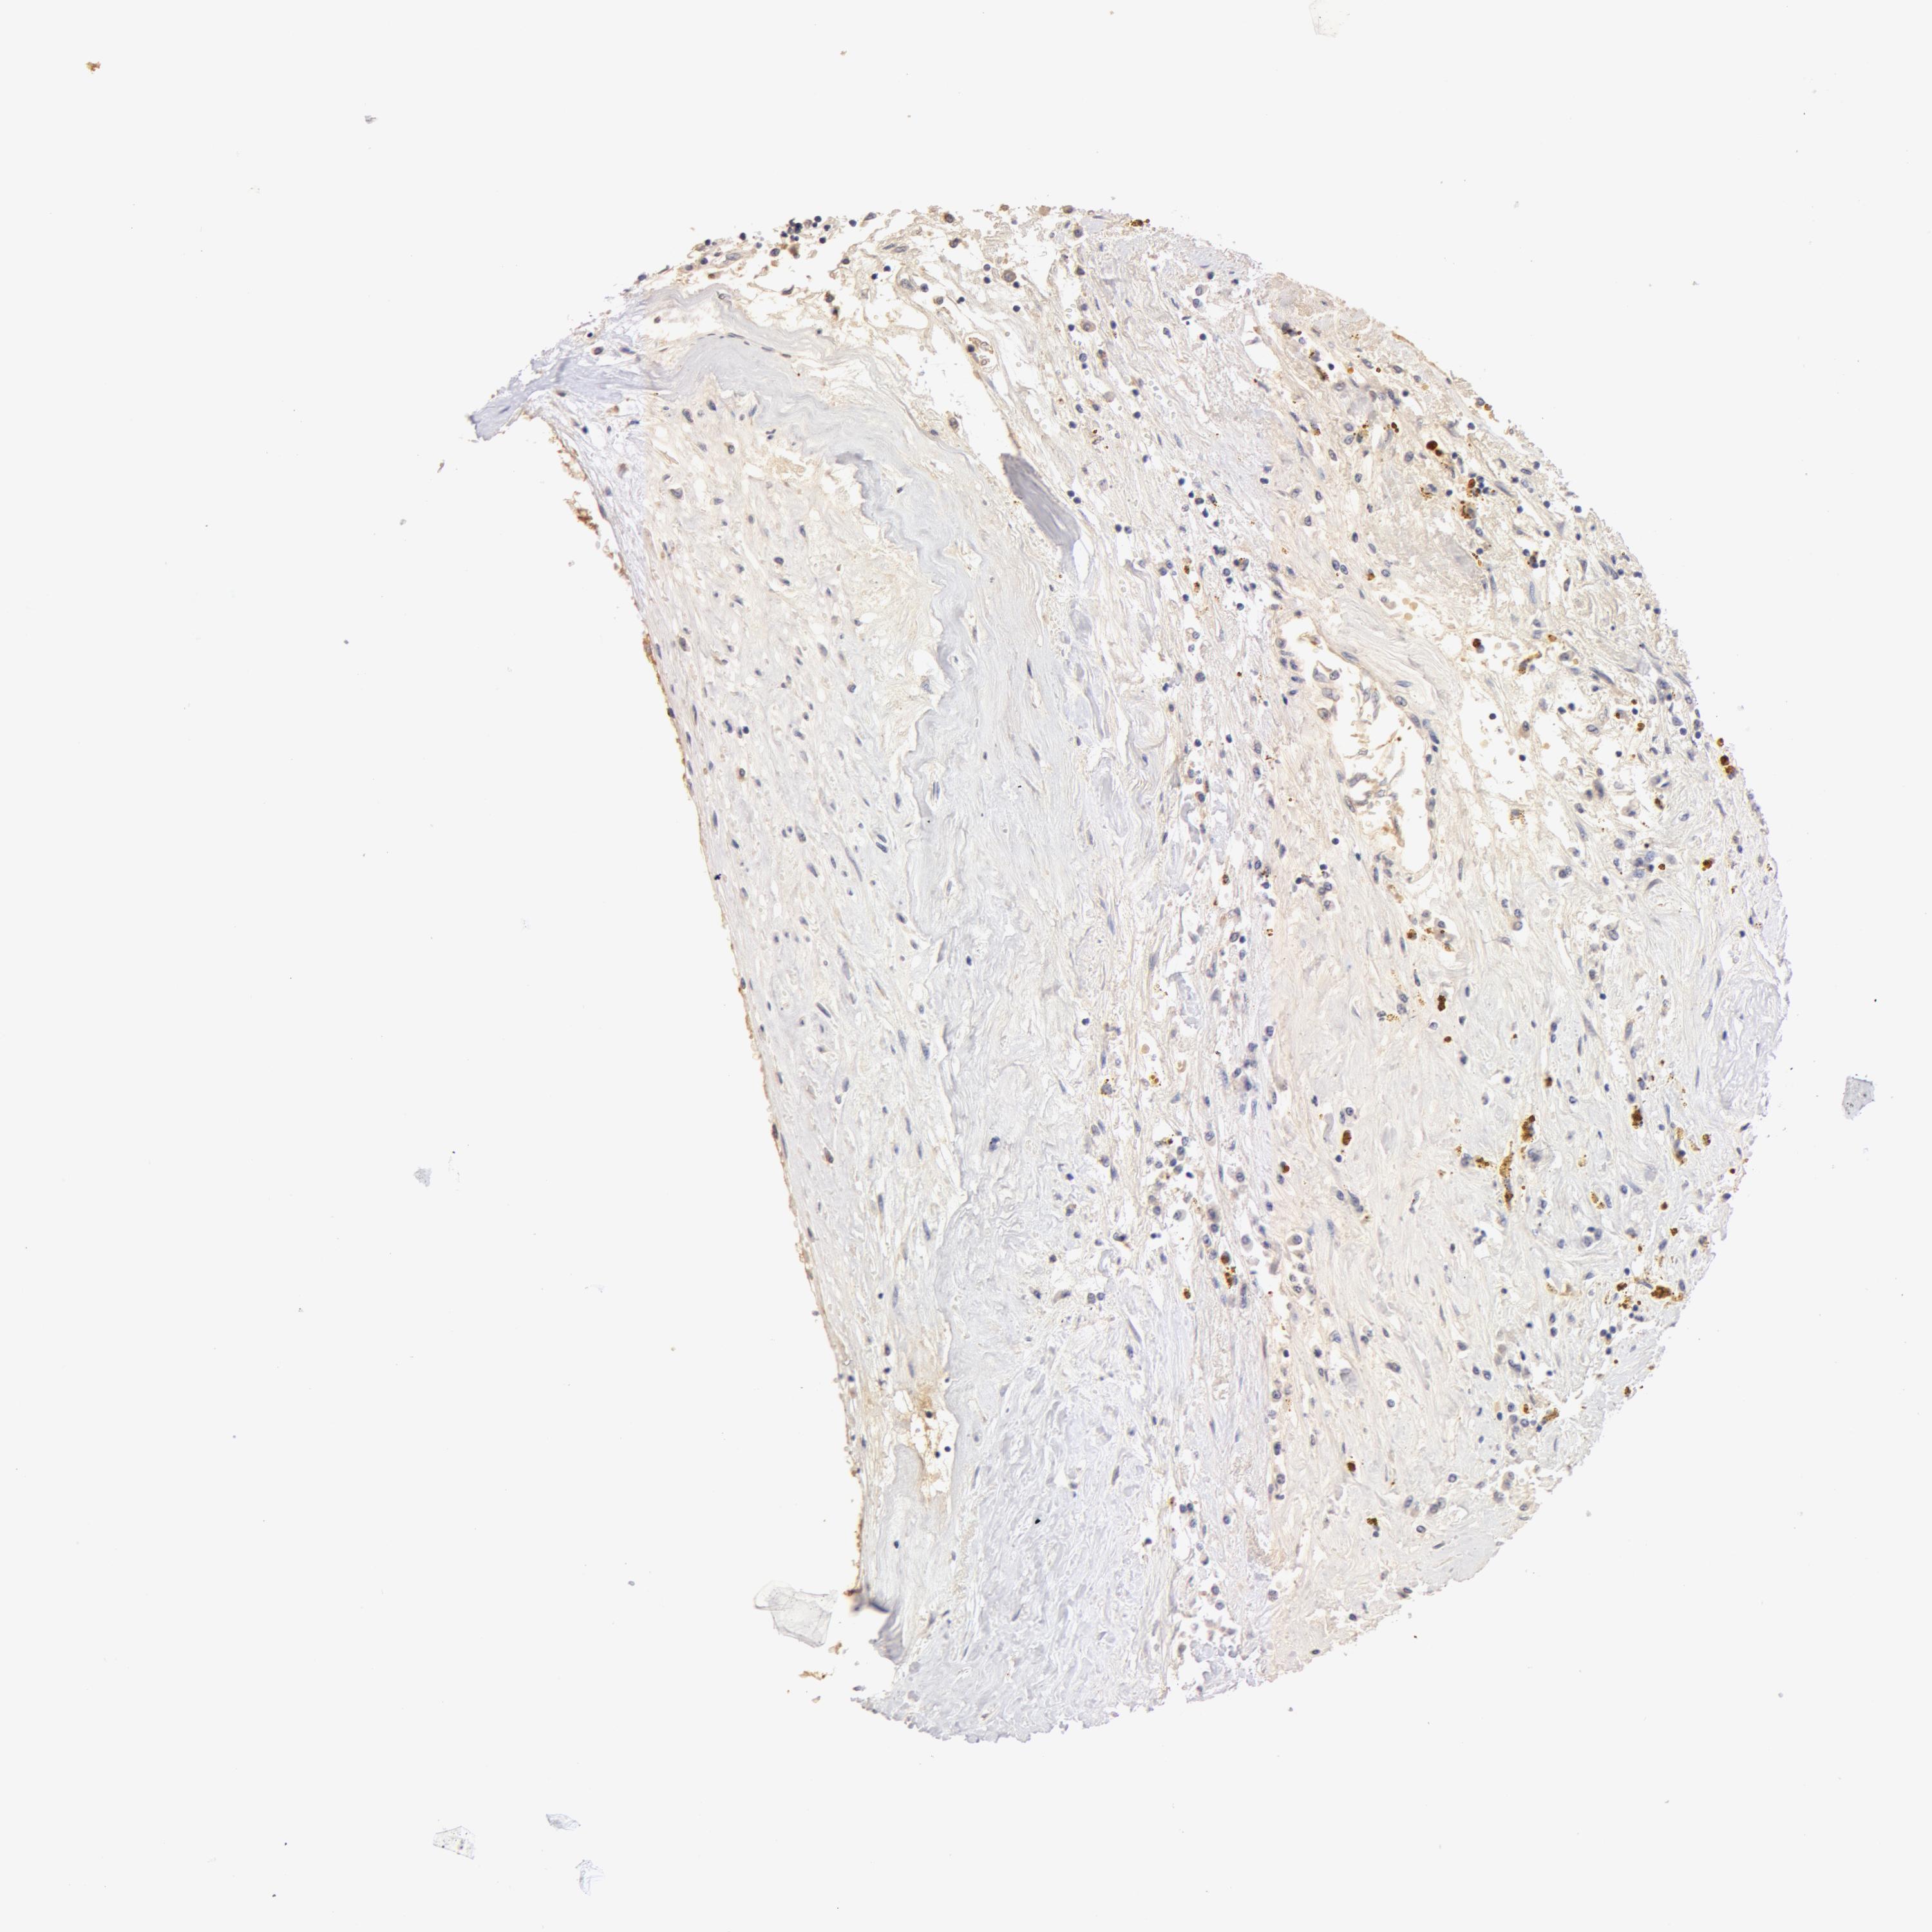

KIDNEY RENAL CLEAR CELL CARCINOMA (VALIDATION) - Interactive survival scatter ploti

The Survival Scatter plot shows the clinical status (i.e. dead or alive) for all individuals in the patient cohort, based on the same data that underlies the corresponding Kaplan-Meier plots. Patients that are alive at last time for follow-up are shown in blue and patients who have died during the study are shown in red.

The x-axis shows the expression levels (FPKM) of the investigated gene in the tumor tissue at the time of diagnosis. The y-axis shows the follow-up time after diagnosis (years). Both axes are complimented with kernel density curves demonstrating the data density over the axes. The top density plot shows the expression levels (FPKM) distribution among dead (red) and alive patients (blue). The right density plot shows the data density of the survived years of dead patients with high and low expression levels respectively, stratified using the cutoff indicated by the vertical dashed line through the Survival Scatter plot. This cutoff is automatically defined based on the FPKM cutoff that minimizes the p-score. The cutoff can be changed by dragging the vertical line or by entering a cutoff value in the square labeled "Current cut-off".

Under the Survival Scatter plot the p-score landscape (black curve; left axis) is shown together with dead median separation (red curve; right axis). Dead median separation is the difference in median mRNA expression between patients who have died with high and low expression, respectively. It is calculated as follows: median FPKM expression of dead patients with high expression - median FPKM expression of dead patients with low expression. This is intended to aid the user in visually exploring custom cutoffs and the associated p-scores and dead median separation.

Individual patient data is displayed and can be filtered by clicking on one or more of the category buttons on the top of the page. Categories describing expression level and patient information include: high, low, alive, dead, female, male and tumor stages. The scale of the x-axis can be toggled between linear and log-scale by clicking on the "x log" button. Mouse-over function shows TCGA ID, patient information and mRNA expression (FPKM) for each patient.

& Survival analysisi

Kaplan-Meier plots summarize results from analysis of correlation between mRNA expression level and patient survival. Patients were divided based on level of expression into one of the two groups "low" (under cut off) or "high" (over cut off). X-axis shows time for survival (years) and y-axis shows the probability of survival, where 1.0 corresponds to 100 percent.

TF is not prognostic in Kidney Renal Clear Cell Carcinoma (validation)

Best expression cut offi

Based on the FPKM value of each gene, patients were classified into two groups and association between prognosis (survival) and gene expression (FPKM) was examined. The best expression cut-off refers the FPKM value that yields maximal difference with regard to survival between the two groups at the lowest log-rank P-value. Best expression cut-off was selected based on survival analysis .

When clicking on this number, the vertical dashed line indicating cut-off, the interactive survival plot, and the Kaplan-Meier curve will be adjusted to show results based on the best expression cut-off.

: 1.65

TCGA RNA samplesi

RNA-seq data is reported as average FPKM (number Fragments Per Kilobase of exon per Million reads), generated by the The Cancer Genome Atlas (TCGA) .

Normal distribution across the dataset is visualized with box plots, shown as median and 25th and 75th percentiles. Points are displayed as outliers if they are above or below 1.5 times the interquartile range. FPKM values of the individual samples are presented next to the box plot.

Average pTPM 14.7

Number of samples 100